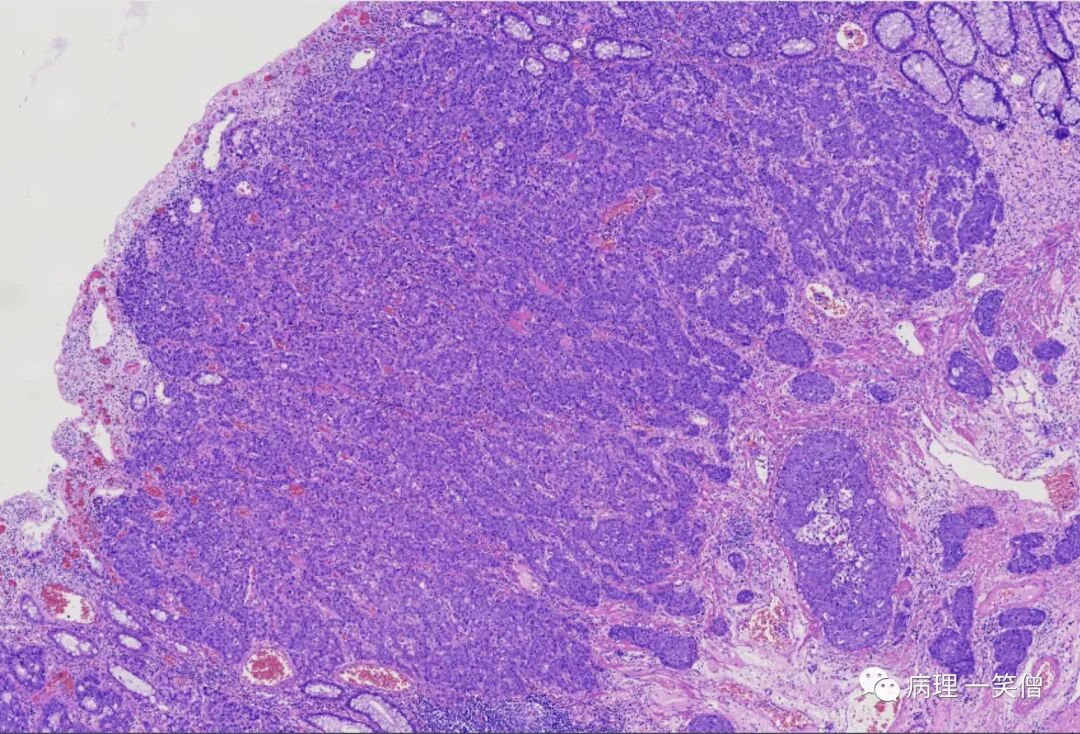

M 65Y 直肠肿瘤

(直肠)双向分化癌(amphicrine carcinoma)。